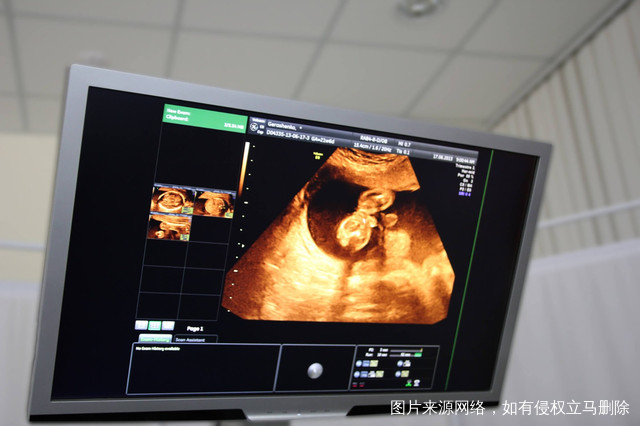

当我们要检查不孕不育的时候,大家一定要看一下具体花销,一般来讲现在的不孕不育费用基本上都是几百元到1000元左右,如果夫妻双方有正常性生活,但是在一年性生活之后依然没有怀孕的,就应该检查一下男性精液情况,女性要在检查这一方面做好内分泌检查,月经干净的三天到5天,一定要做好所有阴道的动态数字化检查以及输卵管的造影检查,还有阴道的四维彩超检查,一般来讲在进行了这样的检查之后就能够确诊。

当女性进入到成熟期之后,每一个月经周期一般来说只有一个卵泡发育成熟,这样就能够排出卵子排卵,通常来说发生在两次月经的中间,也就是说在下一次月经来潮的14天左右,表明双侧的卵泡并不是同时工作的,只要有一侧附件正常就有可能会怀孕,但是也肯定要比双侧附件正常怀孕的成功概率低一点,所以说卵子在这方面至关重要。